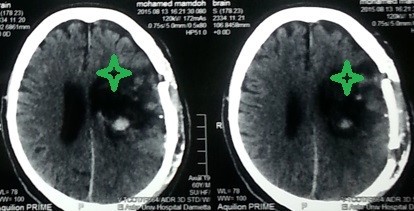

نزيف بالنصف الكروي الايسر بالمخ ممتد لبطينات المخ

hemorrhage in the left hemisphere of the brain extending to the ventricles of the brain

A case of a patient in the sixth decade of life suffering from chronic high blood pressure who had a sudden deterioration in the degree of consciousness with hemispheric weakness. By doing a CT scan on the brain, he found severe bleeding in the left hemisphere of the brain, extending to the ventricles of the brain. A successful microscopic surgery was performed to empty the bleeding, after which the patient returned to his normal state.